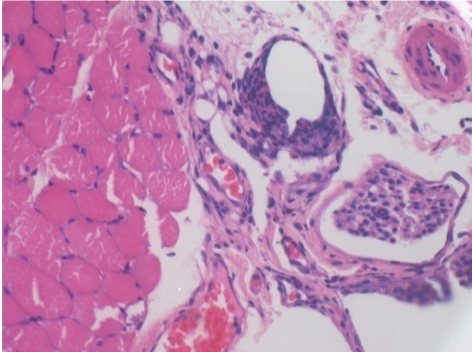

0.5 ml ( 5x 0.1ml) Endopeel SC Injection in the right subcutaneous pretibial area.

R-D90-SC-200X

R-D210-SC-200X

R-D210-SC-400X